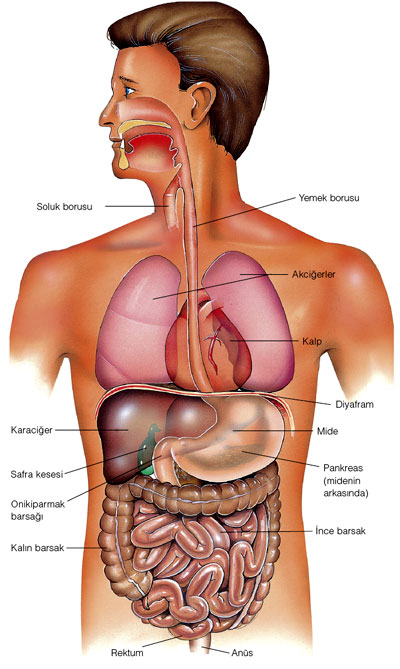

Röntgen sonucunda hastanın kalp, mide ve bağırsaklarının normal konumlarının tersine, sağ tarafta bulunduğu ortaya çıktı. Bu nadir olayı öğrenen doktor ve röntgen uzmanı, durumu tıp camiasıyla paylaşmaya karar verdi. Olayın genetik boyutunu da araştırmak amacıyla hastanın anne-babası ve çocukları da muayene edilerek irsi bir durum olup olmadığı tespit edilecekti. Bu vaka, tıp literatüründe oldukça nadir görülen bir durum olarak tarihe geçti.